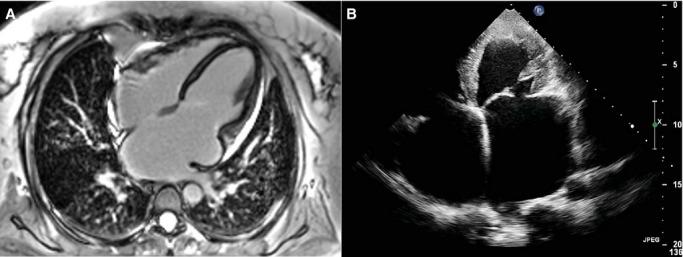

A proband from a multigenerational family with 3 live patients and 1 unrelated patient with clinical diagnoses of RCM underwent a next-generation sequencing workflow based on a custom AmpliSeq panel, including 64 candidate pathogenic genes for cardiomyopathies, on the Ion Personal Genome Machine high-throughput sequencing benchtop instrument. The selected panel contained a total of 64 genes that were reportedly associated with inherited cardiomyopathies. All patients fulfilled strict criteria for RCM with clinical characteristics, echocardiography, and/or cardiac magnetic resonance findings. The multigenerational family with 3 adult RCM patients carried an identical nonsense MYBPC3 mutation, and the unrelated patient carried a missense mutation in the MYBPC3 gene. All of these results were confirmed by the Sanger sequencing method.